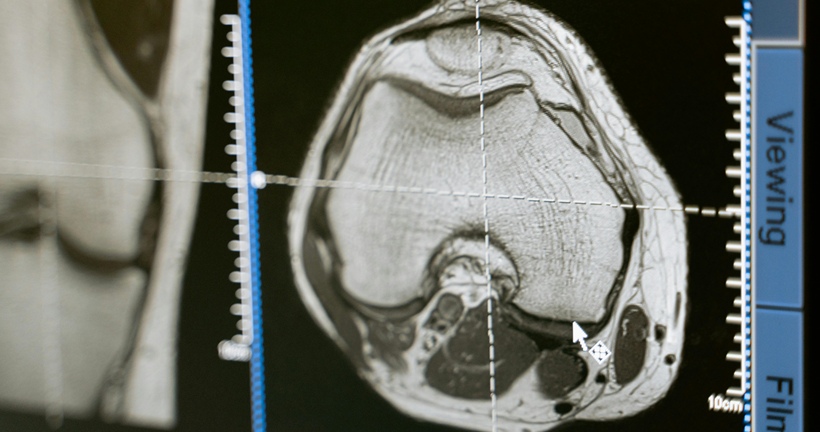

Cristian SantiagoJácome Granda | Investigador La demencia frontotemporal (DFT) es una enfermedad neurodegenerativa compuesta por un conjunto de síntomas comportamentales y del lenguaje como consecuencia de la atrofia de áreas que pertenecen a lóbulo temporal y frontal. Según las características clínicas, la DFT se subdivide en tres variantes. La demencia frontotemporal variante semántica (DFTvnf) que se presenta con alteraciones en el lenguaje, principalmente en la capacidad de comprender y reconocer objetos. La demencia frontotemporal no fluente (DFTvnf) se manifiesta por una marcada disminución en la fluidez, fallo en la emisión de sonidos, así como agramatismo y la demencia frontotemporal variante conductual (DFTvnf) de la cual haremos énfasis en esta investigación, es una enfermedad neurodegenerativa poco estudiada y de inicio insidioso, que se caracteriza por la presencia de síntomas comportamentales y cognitivos que repercuten en el desenvolvimiento adecuado en las distintas actividades de la vida diaria. Dentro de la clínica presentada por pacientes que presente este tipo específico de variante se encuentra disfunción ejecutiva, apatía y desinhibición, además de la disminución en la empatía, alteraciones en los hábitos alimenticios y conductas estereotipadas marcadas, en ocasiones, se manifiesta mediante comportamientos compulsivos y conductas sexuales desinhibidas; los sujetos pueden presentarse agresivos, con una higiene personal desalineada, hiperoralidad, así como coprolalia. A pesar de que este cuadro es el más frecuente, existen perfiles caracterizados por la adinamia y la falta de iniciación. La presentación sintomatológica de la disfunción frontal dependerá de si la afectación predominante inmiscuye a regiones del cíngulo u orbitales. Además, las afectaciones de las funciones ejecutivas dependerán del daño en la corteza dorsolateral. Buscamos describir la relación existente entre la atrofia cerebral identificada en estudios de resonancia magnética estructural, PET-FDG y su implicación cognitiva sobre los pacientes con DFTvnf. La revisión sistemática se realizó bajo los criterios establecidos en la declaración PRISMA, considerando 80 estudios de las bases de datos Pubmed y ScienceDirect en donde por criterios de inclusión y exclusión la revisión final se realizó con 40 artículos de las bases de datos antes descritas. Como resultados en relación con los estudios analizados, se encontró que solo el 15% de artículos mantienen una correlación de áreas anatómicas - cognitivas, además se encontraron alteraciones en los dominios de atención, memoria y funciones ejecutivas mientras que los hallazgos de atrofia cerebral se localizan en áreas frontales, el cíngulo e ínsula. El diagnóstico de la DFTvnf es un proceso complejo que se compone de distintas etapas, por lo que, la presente revisión sistemática confirma la importancia de estudio de las manifestaciones clínicas, la evaluación neuropsicológica de procesos cognitivos y el papel de las técnicas de neuroimagen en la identificación de este tipo de variantes. Estos resultados contribuirán a obtener un diagnóstico oportuno y veraz de la DFTvnf, describir las manifestaciones clínicas de manera más específica además de beneficiar a los profesionales del área para la implementación de intervenciones adecuadas que permitan mejorar la calidad de vida de quienes la padecen. Leer el artículo completo

DR. CRISTIAN E. LEYTON Y DR. RAMÓN LANDIN-ROMERO | FACULTY OF HEALTH SCIENCES, THE UNIVERSITY OF SYDNEY. SYDNEY, AUSTRALIA. En los últimos años el interés científico en las enfermedades neurodegenerativas ha crecido considerablemente. Esto ha sido motivado por el gran incremento en el número de personas afectadas por estas dolencias, unido al advenimiento de nuevas técnicas y métodos de evaluación que han posibilitado un mejor conocimiento sobre las mismas. En los últimos 10 años, grupos internacionales de investigadores han actualizado los criterios diagnósticos de demencia, incorporando el uso de imágenes cerebrales y otros marcadores biológicos en la valoración del juicio clínico. Las demencias frontotemporales son un conjunto amplio y heterogéneo de enfermedades neurodegenerativas que afectan frecuentemente a pacientes menores de 65 años. Se manifiestan a nivel clínico con cambios graduales en la personalidad y en el lenguaje, a diferencia de la enfermedad de Alzheimer que se asocia a una pérdida gradual de la memoria. Las demencias frontotemporales también se asocian con la acumulación tóxica de al menos dos proteínas distintas en las neuronas, mientras que la enfermedad de Alzheimer se caracteriza exclusivamente por la acumulación de ovillos neurofibrilares y placas de amiloideas en el cerebro. De acuerdo con la prominencia de las manifestaciones clínicas, las demencias frontotemporales pueden clasificarse en dos grandes grupos; la variante conductual y la variante afásica, esta última también referida como afasia progresiva primaria. La variante conductual cursa con cambios larvados de la personalidad y comportamiento. Estos síntomas son a veces difíciles de determinar y cuantificar, debido a que su valoración clínica depende del relato del cónyuge, familiares, amigos o colegas del paciente. Frecuentemente los familiares relatan conductas sociales inapropiadas, pérdida del decoro y cortesía, como también falta de empatía y contacto social, y pérdida de interés en pasatiempos. En muchos casos, las alteraciones conductuales dan lugar a conflictos conyugales, problemas interpersonales o dificultades laborales que pueden camuflar los síntomas primarios de la enfermedad y retrasar el diagnóstico. Debido a que este tipo de demencia afecta mayoritariamente a personas menores de 65 años, los síntomas también se pueden confundir con crisis existenciales, episodios depresivos, trastorno bipolar u otras alteraciones psiquiátricas propias de esta edad. La evaluación de las funciones mentales superiores, de gran relevancia en la demencia frontotemporal, se efectúa mediante una evaluación neuropsicológica. Ésta puede evidenciar deterioros en la capacidad para ejecutar actividades complejas que requieren habilidad de planificación, jerarquización y resolución de conflictos. No obstante, la evaluación de estas habilidades (también conocidas como funciones ejecutivas) presenta ciertas limitaciones, ya que muchos pacientes con demencia frontotemporal muestran un rendimiento limítrofe o dentro del rango normal en comparación con personas sanas de la misma edad. Nuevas técnicas como la resonancia magnética nuclear, permiten visualizar la anatomía del cerebro con gran detalle en pacientes con demencia en vida. El estudio de resonancia cerebral es además fundamental para descartar otras posibles causas de demencia, como la presencia de tumores o de enfermedad cerebrovascular. Las imágenes de resonancia en pacientes con demencia frontotemporal detectan una reducción significativa del tamaño de la parte delantera del cerebro, que incluye la parte inferior de los lóbulos frontales y la parte anterior de los lóbulos temporales. Sin embargo, en estadios temprano de la enfermedad, los cambios cerebrales son sutiles y muchas veces el clínico debe observar la progresión de los síntomas para establecer un diagnóstico certero. La ausencia de síntomas clínicos claramente definidos ha motivado que los criterios diagnósticos actuales estratifiquen el grado de certeza diagnóstico en tres niveles; definitivo, posible y probable. El diagnóstico definitivo se establece cuando el examen histológico revela cambios patológicos en el cerebro y/o cuando existe en el paciente una mutación genética causante de la enfermedad. El diagnóstico posible se establece ante la presencia progresiva de los cambios conductuales y/o fallos en pruebas neuropsicológicas. Por último, el diagnóstico probable requiere además la presencia de cambios en las imágenes cerebrales y un deterioro funcional significativo en las actividades de la vida diaria. En el otro espectro clínico de la demencias frontotemporales están las afasias primarias progresivas. En contraste con la variante conductual, las afasias progresivas presentan un deterioro progresivo del lenguaje que es bastante evidente para el paciente y familiares. Característicamente, las alteraciones del lenguaje son relativamente aisladas y respetan otros dominios cognitivos, al menos durante las fases iniciales de la enfermedad. La presentación afásica, sin embargo, exhibe un amplio rango de alteraciones del lenguaje que afectan la capacidad para comprender o producir palabras u oraciones adecuadamente. Los criterios actuales definen tres variantes clínicas; semántica, no-fluente/agramática y logopénica, cada una de las cuales presentan un patrón único de alteración lingüística, distribución de atrofia cerebral y patología asociada. La variante más enigmática es la variante semántica o también conocida como la demencia semántica. La alteración lingüística cardinal es la pérdida del significado de las palabras y una reducción del vocabulario, que es reflejo de una disolución del conocimiento conceptual sobre el mundo. La demencia semántica se asocia a una desintegración de la información enciclopédica que se acumula a largo de la vida que causa dificultades no sólo para reconocer objetos y palabras, sino que también para identificar a las personas, sonidos y canciones. Las personas con demencia semántica pueden pasar desapercibidas, ya que presentan un lenguaje fluido, se incorporan con facilidad a una conversación y realizan actividades cotidianas de forma normal, al menos al inicio de la enfermedad. Las imágenes cerebrales muestran de manera consistente una reducción del tamaño de la parte anterior de los lóbulos temporales y la patología microscópica muestra la acumulación anormal de una proteína llamada ‘TDP-43’. La variante no-fluente/agramática, como su nombre lo indica, se caracterizada por dificultades para articular palabras, y construir y comprender oraciones. Sin embargo, al contrario de la variante semántica, la comprensión del vocabulario está preservado. Las imágenes cerebrales muestran una reducción de la masa cerebral de la parte inferior del lóbulo frontal izquierdo (área de Broca), un área que tiene un rol establecido en el habla y procesamiento morfosintáctico. La patología microscópica muestra acumulación anormal de una proteína llamada ‘tau’. Finalmente, la variante menos conocida, pero no menos importante, es la afasia logopénica, cuyo vocablo es derivado del griego y literalmente significa “escasez de palabras”. Como su nombre lo indica, las personas con la afasia logopénica presentan dificultades para encontrar palabras, lo que genera constante interrupciones y circunlocuciones. En contraste con otras variantes, no hay distorsiones en el habla y el conocimiento de las palabras está preservado. Sin embargo, estos pacientes muestran dificultades para evocar las palabras a pesar de conocerlas. En algunos casos, la construcción de las palabras es defectuosa debido a la transposición, reemplazo o desplazamiento de sílabas, que se hace más evidente con palabras más largas. La repetición de oraciones está consistentemente alterada, no solamente debido a los errores silábicos mencionados, sino que también por la incapacidad de retener todos los componentes de la oración en la memoria de corto plazo. Las imágenes cerebrales demuestran atrofia de la parte lateral del hemisferio izquierdo, en la unión entre el lóbulo temporal y lóbulo parietal. De forma importante, y en contraste con otras variantes de demencia frontotemporal, la mayoría de los casos de afasia logopénica, se asocian a con cambios microscópicos propios de la enfermedad de Alzheimer. Este hecho es de gran relevancia, ya que demuestra que la enfermedad de Alzheimer puede presentarse sin alteraciones en la memoria, pero con importantes problemas en la producción del lenguaje. En tan solo una década, el mundo de la investigación en demencias ha experimentado un notable desarrollo. Sin embargo, nuevos paradigmas son necesarios para comprender cómo la acumulación de las ciertas proteínas promueve distintos patrones de atrofia cerebral que a su vez dan lugar a la emergencia de diversos síndromes clínicos. Uno de los grandes desafíos de la neurociencia actual es, no solamente la detención del desastroso avance de estas enfermedades, sino además la determinación precoz de los síntomas. La identificación de mecanismos genéticos asociados al riesgo de desarrollar demencia a lo largo de la vida, servirá para implementar a tiempo intervenciones que puedan modificar, o mejor aún, detener la progresión de la neurodegeneración antes de la aparición de los primeros síntomas.